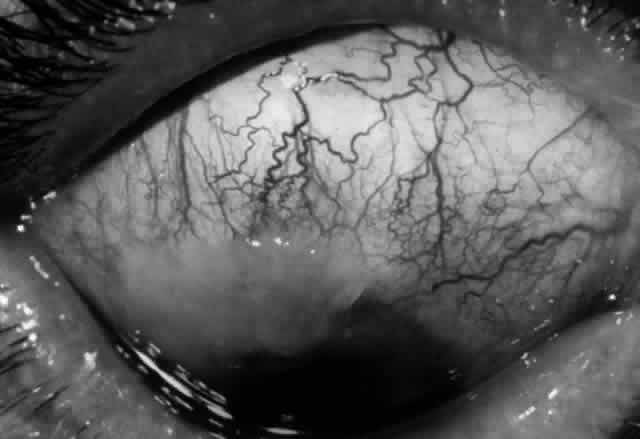

Clinically, the ocular disease in cicatricial pemphigoid (OCP) may present unilaterally in the form of a chronic, recurrent catarrhal conjunctivitis, but it eventually becomes bilateral. Subepithelial fibrosis is characteristic of stage 1 of OCP (Fig. 7). Stage 2 shows fornix foreshortening (Fig. 8), and symblepharon formation is the hallmark of stage 3 (Fig. 9). Stage 4, end-stage disease, is characterized by ankyloblepharon and surface keratinization (Fig. 10). Obstruction of the lacrimal ductules and meibomian gland ducts eventually produces an unstable tear film and progressive sicca syndrome, but it is to be emphasized that OCP is not a dry-eye syndrome until late in the disease course.20 Trichiasis and entropion occur because of the subepithelial fibrosis, with eventual keratopathy, corneal neovascularization, and corneal ulceration and scarring.20

Fig. 8. Stage 2 cicatricial pemphigoid, with fornix foreshortening and subepithelial fibrosis without frank symblepharon formation.